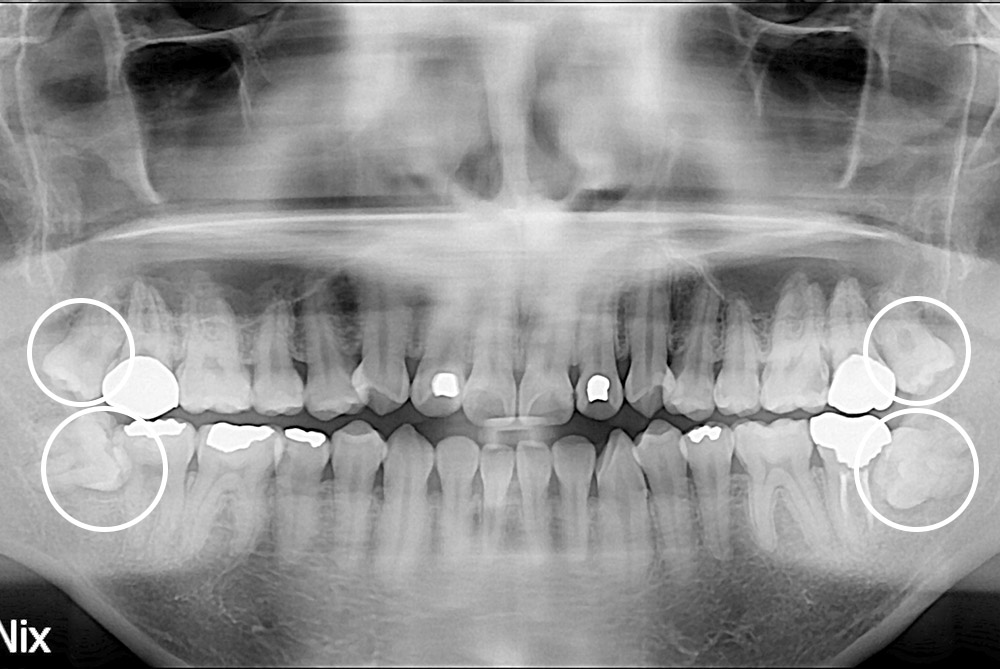

[사랑니] 매복 사랑니 발치

치료전 : 2018-09-18